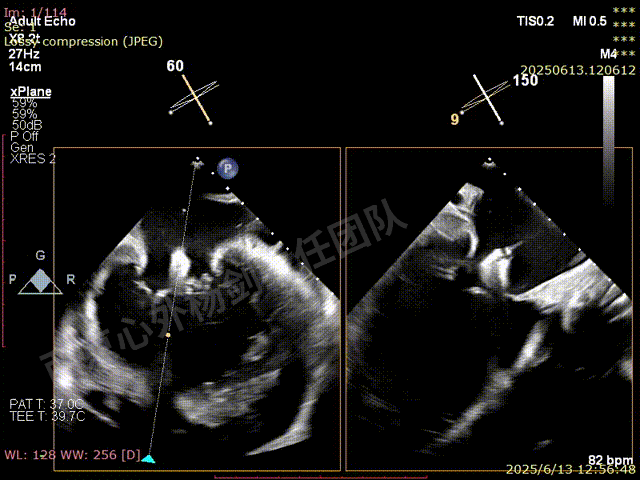

TEER术前超声评估

图片

二尖瓣后叶栓系严重,前叶相对错位,反流束沿2区分布广泛,2偏3区处存在反流。

反流宽度至少23mm,因影像调整困难,考虑实际反流更宽。